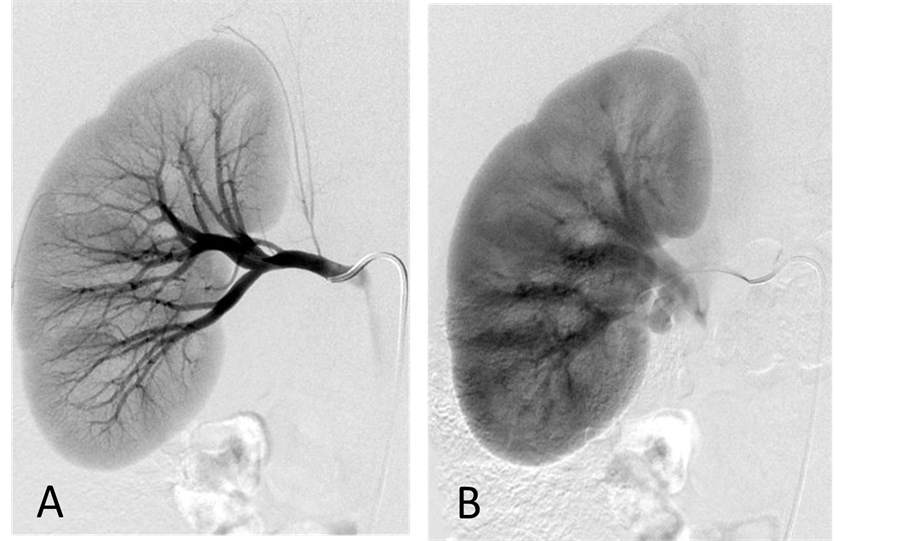

With the patient under general anesthesia, a 5-Fr Omni Flush catheter (Angio Dynamics, Queensbury, NY, USA) was placed in the aorta above the celiac axis from a percutaneous retrograde transfemoral arterial approach, and aortograms were performed, first with 30 cc of CO2 and then in the anterior-posterior (AP) and left anterior-oblique (LAO) projections with Visipaque (GE Healthcare, Cork, Ireland, UK). During each of the runs, there was a moderate increase in blood pressure from baseline systolic pressures of 120 s to 145 - 150 s, lasting 5 minutes, accompanied by bradycardia and transient arrhythmia. A nitroglycerin drip was started; however, the patient did not require any alpha or beta blockers. Next, a 5-Fr shepherd hook catheter (Angio Dynamics, Queensbury, NY, USA) was positioned and digital subtraction angiography (DSA) was performed, sequentially, in the right and left renal arteries, superior mesenteric artery, and finally the celiac axis. The aortograms revealed two vascular retroperitoneal tumors to the right and left of the aorta, at the level of L1-2, measuring 22 mm × 27 mm and 26 mm × 27 mm, respectively (Figure 2(A) and Figure 2(B)). The right retroperitoneal mass was located posteroinferior to the right renal artery and posterior to the inferior vena cava (IVC). The left retroperitoneal mass was located between the left main renal artery and the inferior accessory renal artery. The inferior accessory renal artery supplying the lower pole of left kidney showed diffuse narrowing due to either compression or catecholamine release by the tumor (Figure 3(A) and Figure 3(B)). Subsequently, bilateral renal arteriograms were performed without a hypertensive response to the injection of contrast material. The right main renal artery was displaced by the tumor with mild arterial narrowing (Figure 4(A) and Figure 4(B)). Left renal arteriogram showed a patent main renal artery with a circumaortic renal vein (Figure 5(A) and Figure 5(B)).

Figure 2. (A) CO2 digital subtraction aortogram, arterial phase, showing hypervascular retroperitoneal tumors (arrows) (B) late arterial phase. There is increased CO2 accumulation throughout the tumors (arrows).

Figure 3. (A) Aortogram with iodinated contrast medium in left anterior oblique projection. The tumors show fine neovascularity. The inferior accessory renal artery (arrow) abutting the inferior margin of the tumor shows diffuse narrowing; (B) Capillary phase. There is irregular, increased contrast accumulation throughout the tumors (arrows).